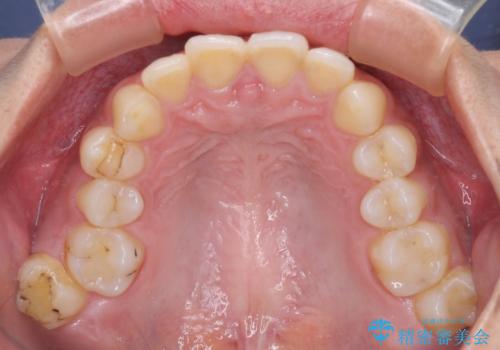

深い咬み合わせと前歯のデコボコ インビザラインによる矯正治療

- 前歯のデコボコと、食いしばりやすい咬み合わせを気にして来院された患者様です。

治療途中では、左右ともに奥歯が咬みにくい状態が続き、問題なく噛めるようになるまでに長期間を要しました。

一方で、デコボコや下顎の前歯が隠れてしまうほどの深い咬み合わせはしっかりと改善されました。